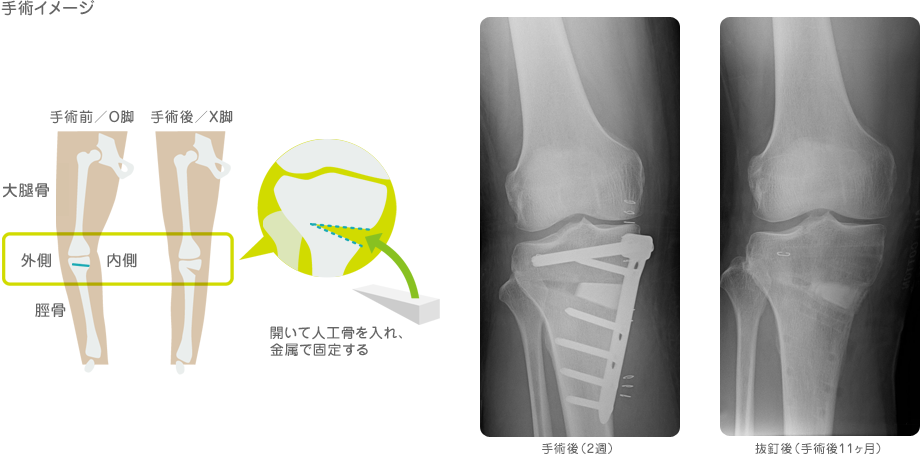

O脚だと、ヒザの内側にある軟骨に過大な不可がかかり、擦り切れてしまって痛みが出ます。そこで、ヒザから下の大きな骨(脛骨)に切れ込みをいれ て、アライメントを変更、外側の軟骨に重心軸をもってくることで、内側の負荷をなくしてしまおう!という超チカラ技的な手術があるんだそうです。

脛骨骨切り術 といいます。今日テレビで見たんですよ。痛そうですね。骨切りって・・・・

骨切り1.png

骨切り2.jpg